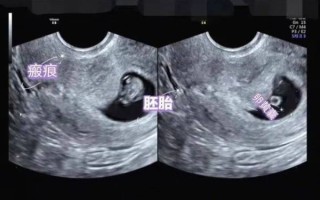

孕妇做b超需要空腹吗_孕早期b超注意事项 不需要空腹,但孕早期经腹B超建议憋尿;孕中晚期通常无需憋尿也无需空腹,除非医生特别说明。 --- 为什么大多数孕妇B超不用空腹? **普通产科超声检查**观察的是子宫、胎盘、羊水及胎儿结... 新网编辑 2025-11-20 33